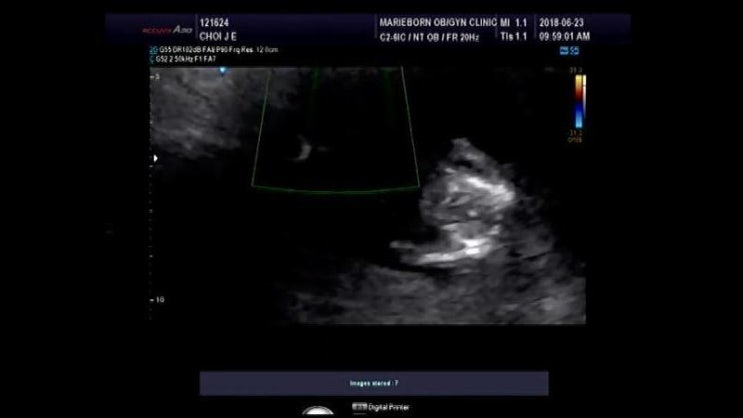

[⚝별하이야기/임신14주-임신16주]별하성별/주수사진/구리 동그라미산후조리원

벌써 #임신16w 5d가 된 예비맘이 되었어요!!~ 2주가 어찌나 그렇게 기다려지는지 우리 별하 성별이 .. 궁금...